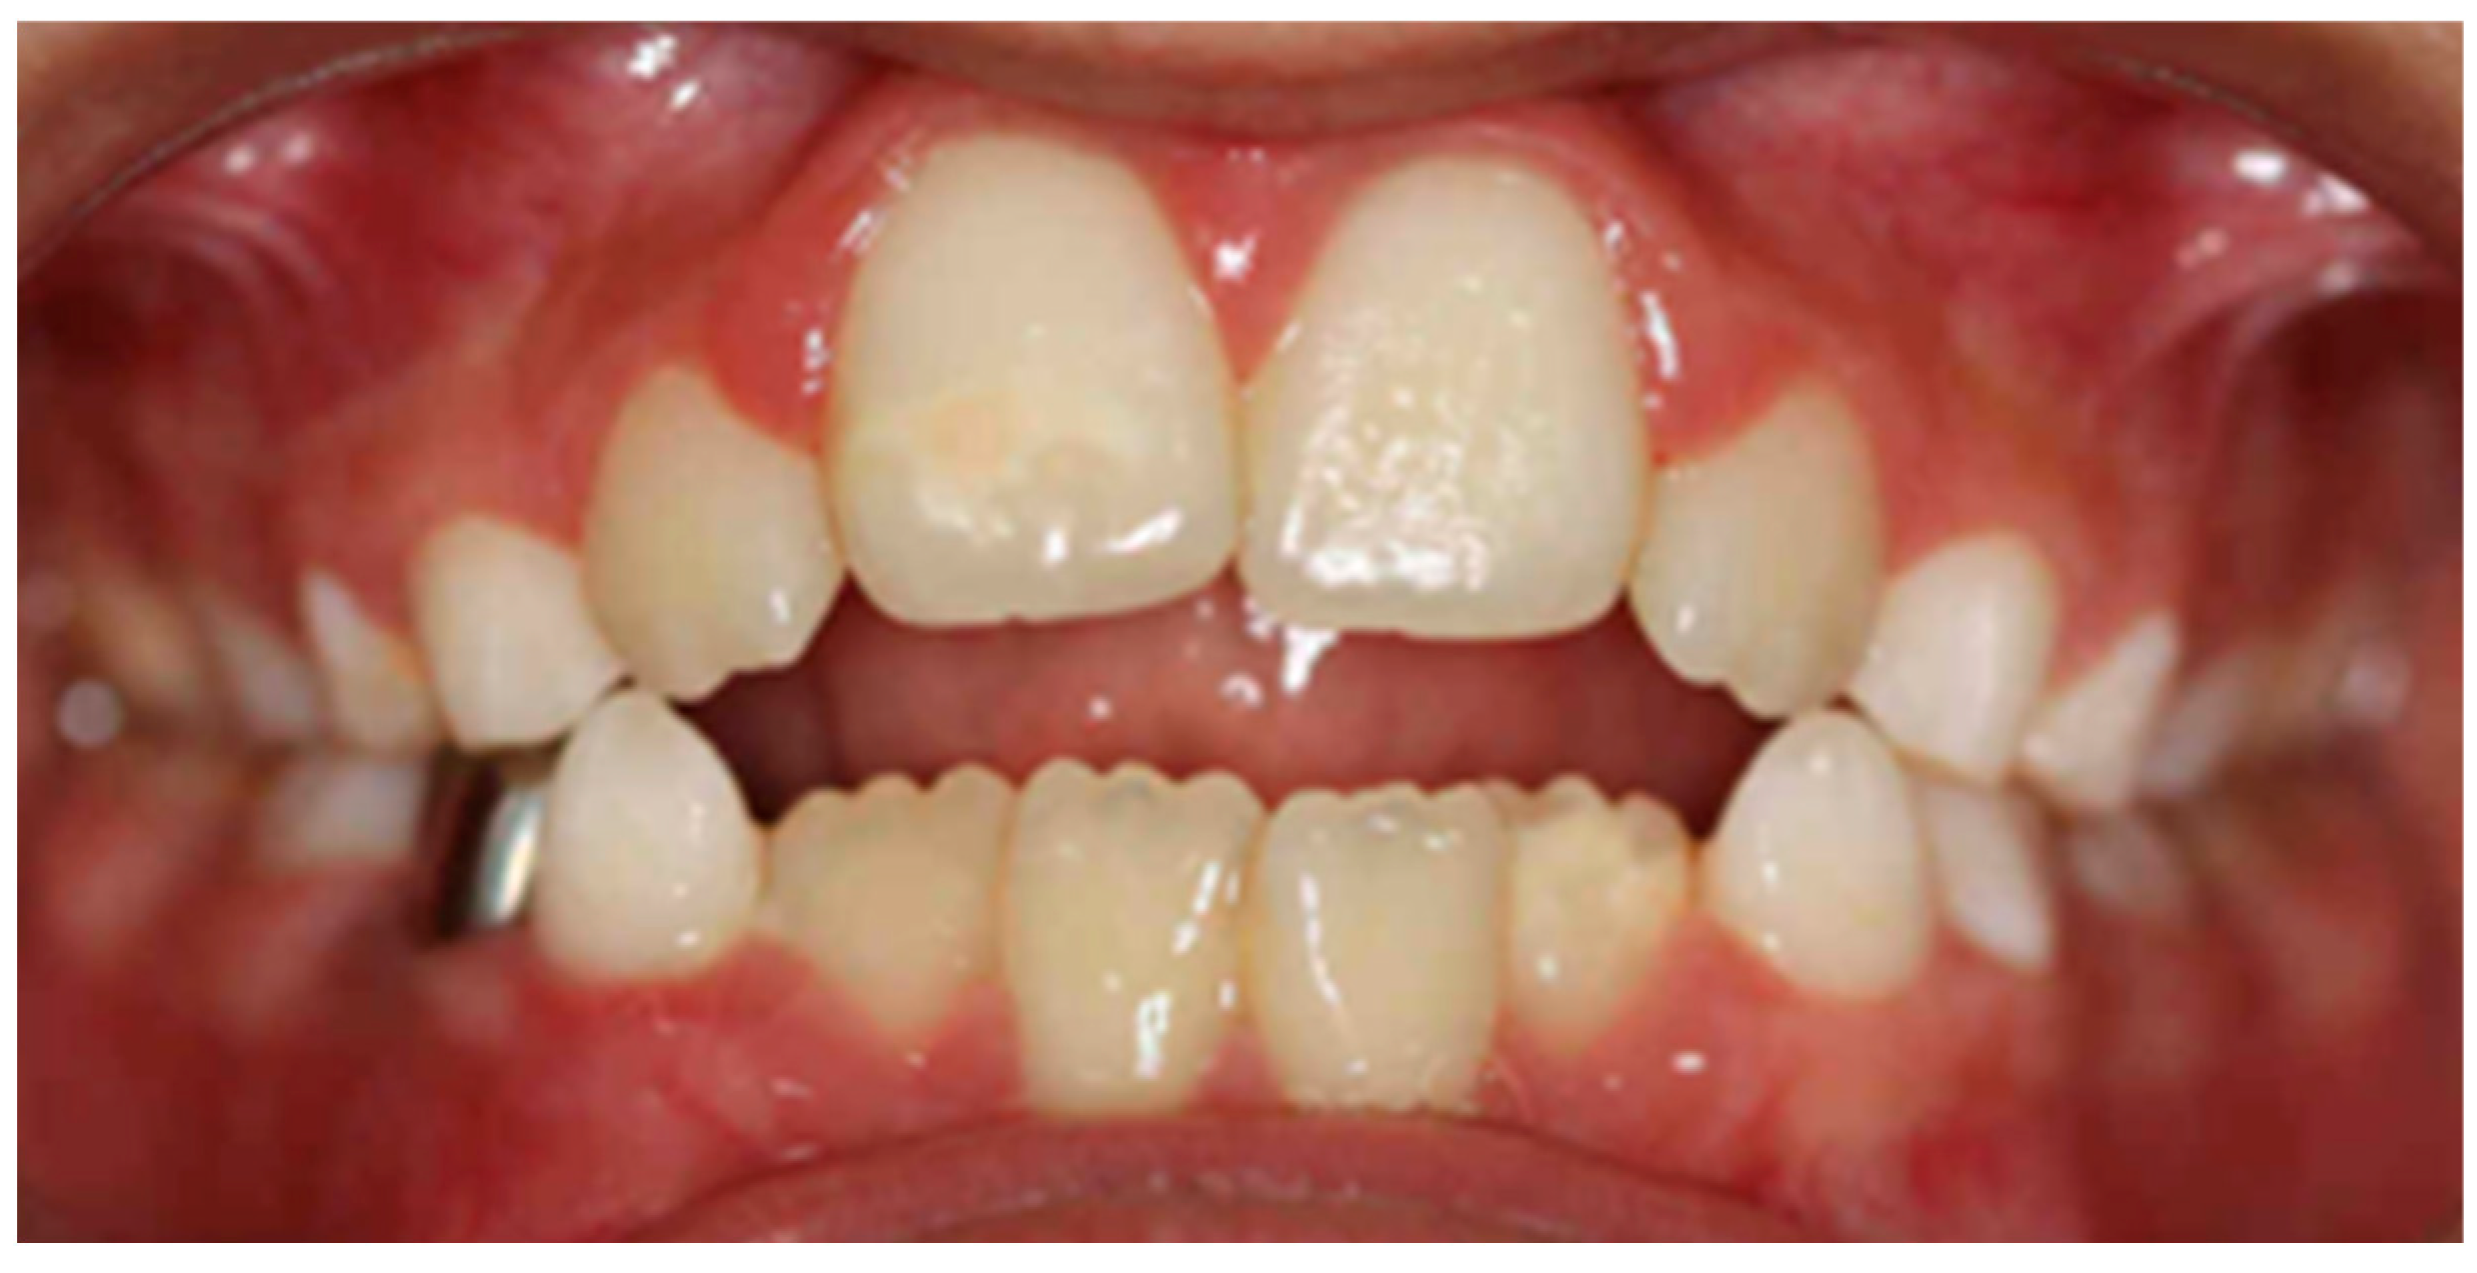

In the vertical plane, it was determined that there is a statistically significant relationship between an immature swallowing habit and malocclusions in the vertical plane (p < 0.05), with an open bite being the most frequent, with a considerable strength of relationship between these variables (V > 0.3) (Figure 2). The same occurs with the lip sucking habit, with which there is a statistically significant relationship with vertical plane malocclusions (p < 0.05) and an intense relationship (V > 0.3) (Table 3).

Figure 2.

Intraoral photograph of an anterior open bite caused by immature deglutition.